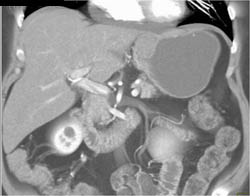

GIST Tumor